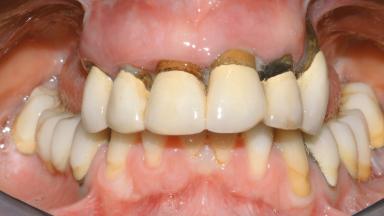

A 35-year-old Caucasian female presenting with advanced periodontal disease involving both the maxillary and the mandibular dentition was referred for evaluation. The patient, a non-smoker in good general health, requested treatment for recurrent periodontal abscesses, tooth mobility, and discomfort during chewing, as well as restoration of her missing teeth with a fixed prosthesis to improve mastication and esthetics. All residual maxillary teeth exhibited plaque deposits, deep pockets, bleeding on probing, and class III mobility and were evaluated as hopeless. All residual mandibular teeth except tooth 37 could be maintained after periodontal therapy.